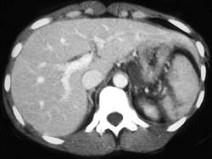

下列图像最佳诊断是 ( )A、脾破裂B、结肠破裂C、胰腺损伤D、小肠破裂E、肝破裂

问题 下列图像最佳诊断是 ( )

选项 A、脾破裂 B、结肠破裂 C、胰腺损伤 D、小肠破裂 E、肝破裂

答案 A